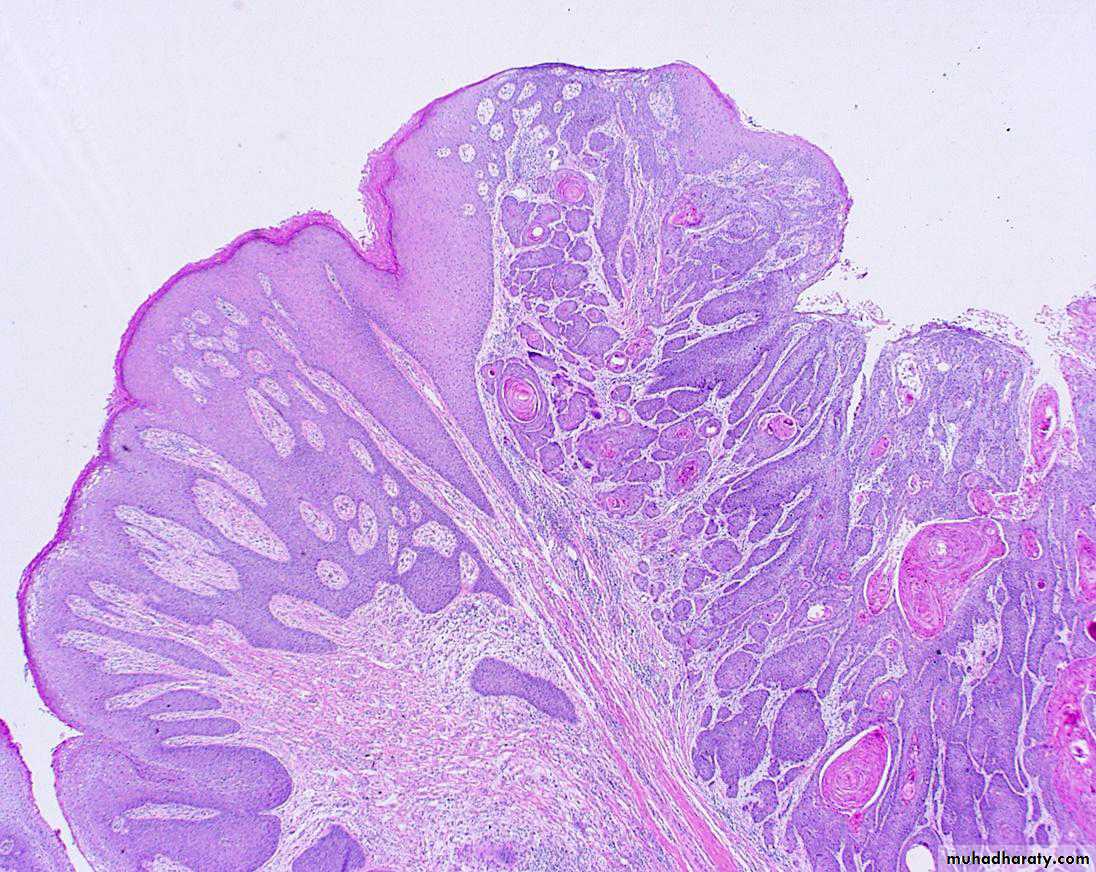

Condyloma acuminatum. Low-power view showing exophytic, papillary architecture.

High-power view reveals HPV cytopathic effect (koilocytic atypia) characterized by atypical, enlarged, hyperchromatic nuclei with perinuclear halos (arrow).Premalignant and Malignant Neoplasms: